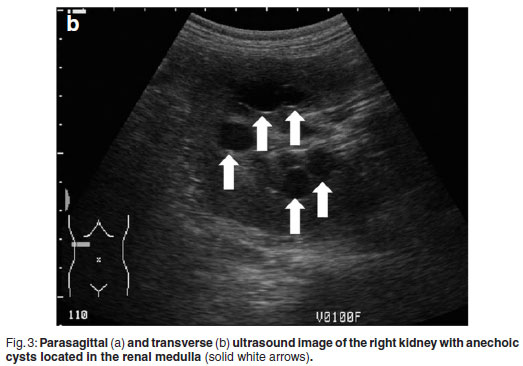

Abdominal ultrasonography was performed under sedation using medetomidine (Domitor, Pfizer, 1 mg/kg) at a dose of 10 µg/kg intravenously. The left kidney measured 10×6×7.5 cm with a slightly uneven margin (cranial pole was larger). A small amount of hypoechoic subcapsular fluid surrounded the kidney. Multiple round, well-marginated, anechoic, cystic structures were seen mainly in the medulla with some extending into the cortex. The largest of these measured 2.5 × 1.5 × 2 cm. These cysts had a clear edge shadow, distal acoustic enhancement with a thin but clear hyperechoic far wall (Fig. 2a,b). Some cysts contained multiple internal hyperechoic specks. The renal cortex was normoechoic and the corticomedullary junction was distinct. Two of the cranial pole cysts of the kidney were more hypoechoic and communicated with a large 5×3×3cm hypoechoic well-marginated, crescentshaped mass which distorted the cranial pole of the kidney. This structure had hyperechoic septa and multiple hyperechoic internal specks that swirled on ballotment. Acoustic enhancement and edge shadowing were seen. Slice thickness artefact was noted in the mass mimicking sediment. No gas was noted in the mass. The right kidney measured 11 × 6 × 5 cm. Multiple smaller (largest about 1×1×1.5 cm) anechoic structures were present mainly in the medulla (Fig. 3a,b). Some of these cysts communicated with each other and some had multiple hyperechoic internal specks. No cysts were found in any of the other abdominal organs, including the pancreas and the liver. The ultrasonographic diagnosis was atypical multiple renal cysts with a suspected large left renal cranial pole cortical abscess. Other individual complicated cysts could not be excluded. The differential diagnosis for cyst-like structures included uniform blood clots, unclotted blood, abscesses without debris, lymphomatous masses and necrosis related to tumours or cystadenocarcinomas35.